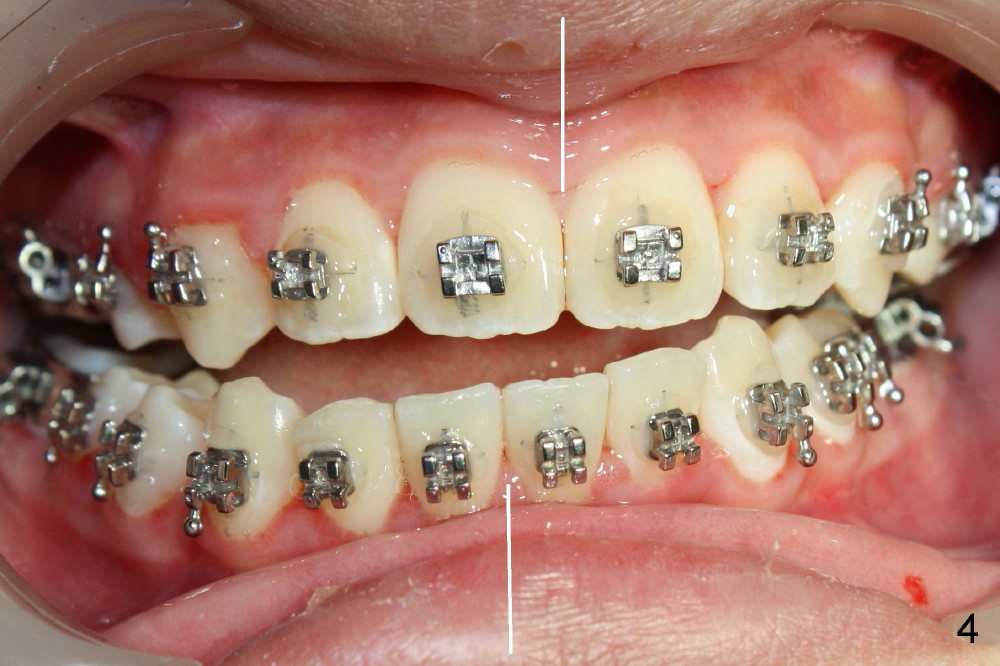

Again due to lack of close monitoring (summer vacation in China), overcorrection occurs (Fig.4-6): from Class II malocclusion to Class III (especially left side (Fig.6 black lines) with anterior open bite and midline shifting (Fig.4 white lines).

The open bite and midline mismatch are discussed

next.